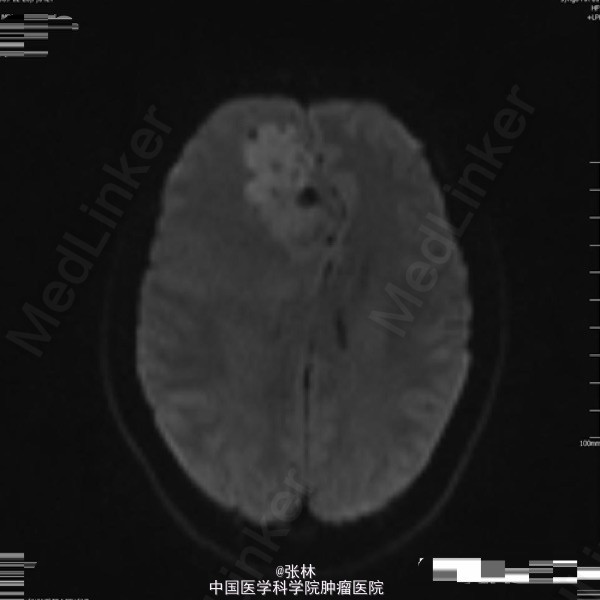

42岁女性,10余天前无明显诱因出现头痛,并呕吐胃内容物,双眼视物模糊。影像学表现:右侧额叶见一不规则形占位性病变,大小约为3.7×4.0×4.5cm,T1WI呈等、低信号,T2WI呈等、高信号,DWI仍呈高信号,周围脑组织少量水肿,增强扫描后病变呈明显强化,边缘水肿无强化。 病理: 镜检:肿瘤细胞弥漫增生,呈乳头状、腺样,细胞核卵圆形,深染。 免疫组化示:GFAP(散在细胞+)、Vimetin(+)、S100(-)、CK(+)、EMA(+)、ki-67(5%+)、CD99(部分+)、CD56(+)、NF(-)、CD34(-)、Hepa(-)、AFP(-)、mammaglobin(-)、RCC(-)、WT-1(-)、CD10(-)、CK7(-)、CK20(-)、Villin(-)、CR(-)、MC(-)、MOC31(-)。及少许脂肪组织,上皮混合组成。 讨论: 室管膜瘤来源于脑室与脊髓中央管的室管膜细胞或脑内白质室管膜细胞巢的中枢神经系统肿瘤。在胶质瘤中占6%,男多于女,多见于儿童及青年,约75%位于幕下,幕上仅占25%。文献报道幕上室管膜瘤75 ~85 %位于脑室外。脑实质内室管膜瘤起源于室管膜细胞嵴,可能是神经管内折叠时形成畸形的结果,好发部位为丘脑,其次为额叶、颞叶、顶叶。实性多见于成人,囊性多见于青少年。 幕上室管膜瘤以头痛、呕吐、嗜睡、厌食及复视等颅高压症状为主,多有局部运动功能障碍和癫痫。